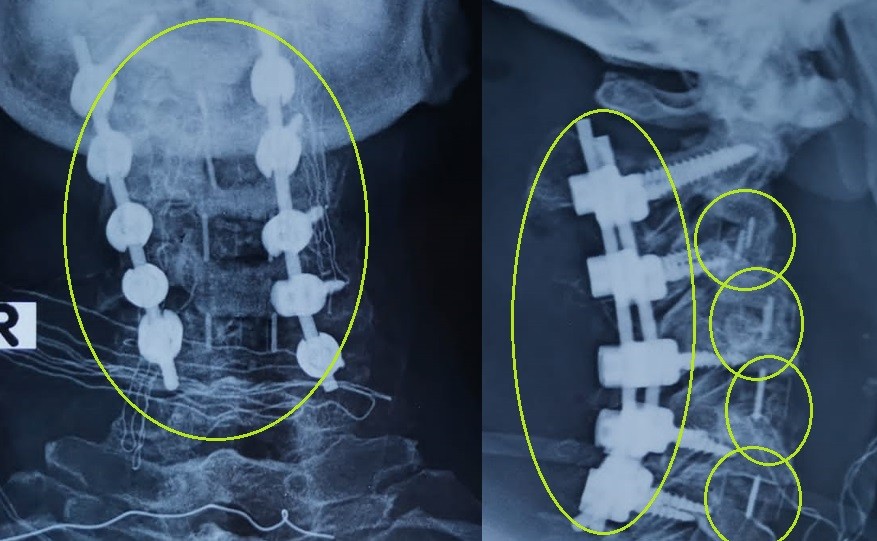

cervical vertebrae kyphosis repair